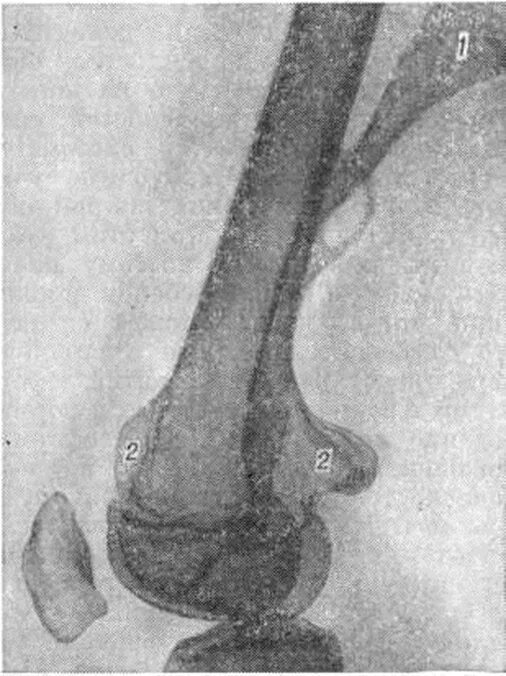

Экзостоз мкб 10